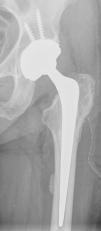

The radiological characteristics of the cement were evaluated with plain X-ray, calibrated with a marker, in anteroposterior projections of the pelvis and axial of the hip, considering cement arteriovenogram to be the radio-opaque images located in the postero-internal face of the proximal femur, with a radiological density close to that of the bone cortex and of linear or serpentine morphology (Table 1). The images suggesting cortical defects were not taken into consideration, and the five cases we found were rejected.

The constancy of the postero-internal location and at a distance that could correspond to the anatomical position of this femoral nutrient bundle should lead us to consider extrusion of the cement towards the veins or arteries that make up the bundle (Fig. 2). Likewise, the linear morphology of the radiographic image suggesting the vessel being occupied by cement, venous valves being observed, differs completely from that produced by a cortical defect or a periprosthetic fracture (Fig. 3), which would result in an irregular image without tubular appearance or the presence of valves.13